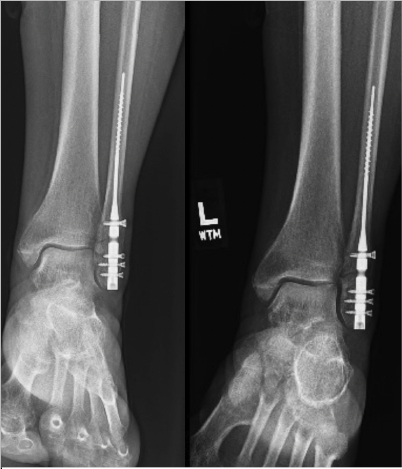

Is there a surgical approach that strikes a happy medium? In our experience, IM fixation for the fibula, while it may not follow the conventional AO techniques, is an appealing alternative to ORIF. Benefits include less anatomic dissection, less prominent hardware, and earlier time to weight-bearing versus the more traditional and historically implemented plate and screw construct.11 IM nails offer relative stability as they do not compress across the fracture site, which deviates from the primary fixation offered by the more traditional ORIF. IM fixation has mostly been reserved for the elderly, patients with diabetes or PVD, or those with significant soft tissue compromise, with the attractive advantages for both the surgeon and the patient. New literature has shed light on the effectiveness and expansion of the utility of IM fixation for fibular fractures (Figure 1).

The key question is then, how does the IM nail compare to a more traditional plate and screw construct for fibular fractures? Numerous studies compare the approaches, most of them very recent, as this technique has garnered popularity. Overall, the literature consistently shows lower complication rates with the fibular IM nail.31,39-41 A 2022 level 1 study found sufficient quality of evidence in the current studies available to conclude that there is no clinical difference between the IM nail and ORIF 12 months postoperatively.42 With that being said, there were reduced complications with the IM nail as previously discussed, and no difference in union rates42 (Figure 2).